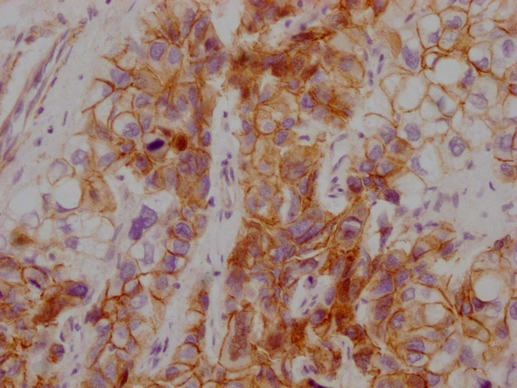

Human tonsil tissue

1:100